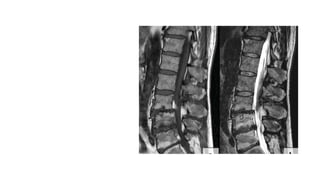

Degenerative

spondylolisthesis

Common - lumbar spine

Less common – C.spine

Never occurs in the thoracic spine.

Grading -

• Based on the ratio of the overhanging part of the superior vertebral

body to the anteroposterior length of the adjacent inferior vertebral

body

Spinal canal stenosis